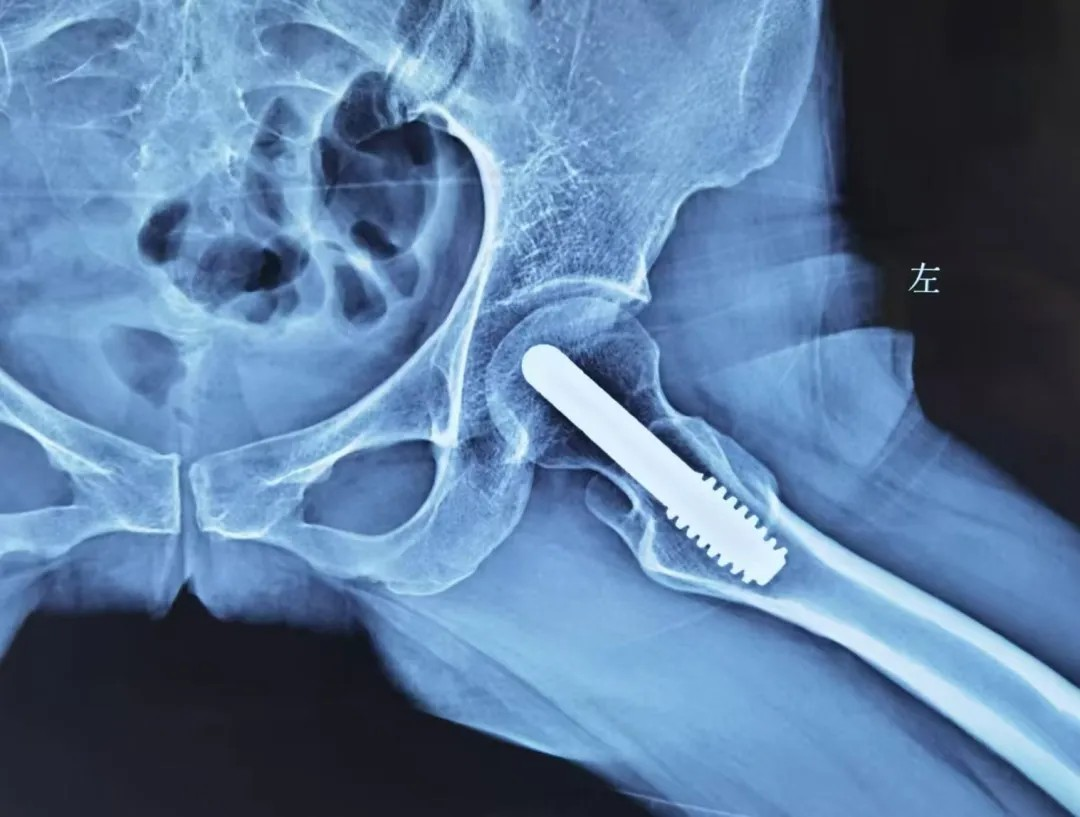

中期:微创 “救” 股骨头

股骨头坏死中期,此时股骨头开始出现小裂缝但没塌陷,可以做微创保髋手术,比如 “髓芯减压术”(钻小孔减轻股骨头内压力)、“植骨术”(填入新骨促进修复),术后配合康复训练,尽可能保留股骨头功能。

若股骨头塌陷轻微,还能尝试 “截骨术”(调整股骨头受力位置);或采取钽棒置入术,即在股骨头中放入钽棒,支撑坏死区域。